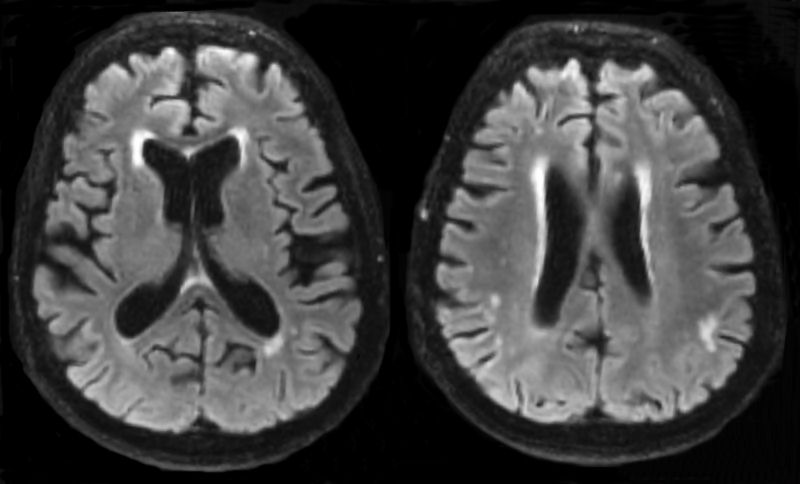

Some other shapes non-characteristic for MS lesions are the so called caps and bands around the ventricles. These are found in almost all elderly people and are not characteristic for MS.

caps